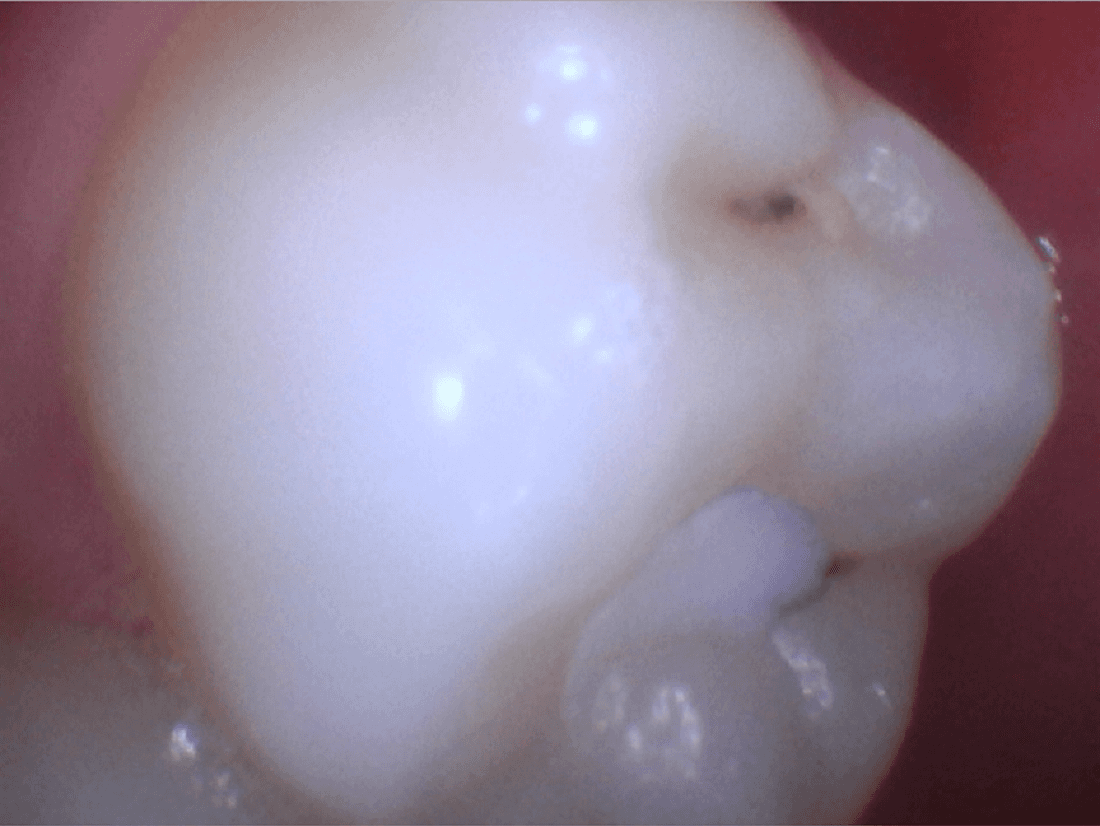

Tooth Colored Fillings for a Natural Looking Tooth

Our practice is based on preventive bread and butter dentistry. We believe that what nature gave you is better than anything we can do. So, we try to do things as conservatively as possible. This example shows a tooth that got a cavity under a sealant which was placed when the patient was a child. Cavities addressed at this stage result in stronger (due to more enamel to bond to) and more longer lasting fillings. The end result looks like a brand new tooth and that' exactly how our patient felt!